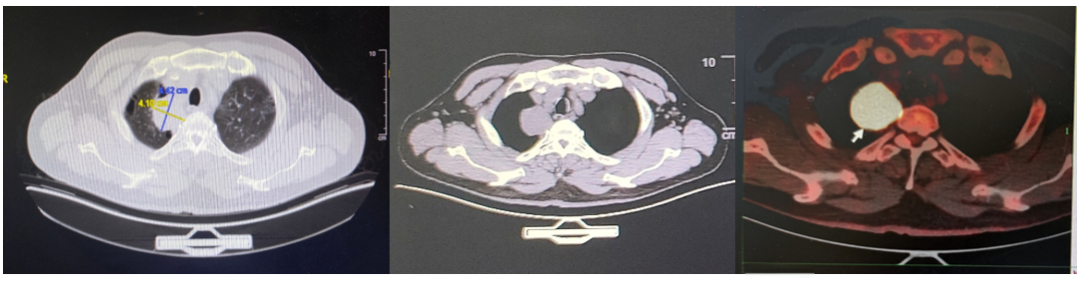

2025年4月15日,CT及PET/CT显示原发灶及全身多发转移淋巴结基本消退,全身多处骨转移灶亦明显好转,局部成骨性骨质改变,未见FDG代谢增高,提示骨修复。疗效评估:完全缓解(CR)。

图片5.png

图5.免疫维持治疗+地舒单抗治疗21月后的PET-CT

图片

图6.免疫维持治疗+地舒单抗治疗后的肺部病灶CT

结合III期临床研究的循证数据、患者治疗效果及患者自身治疗意愿,在免疫治疗+地舒单抗维持治疗~2年,达到CR且病情持续稳定后,综合考虑各方面因素,患者考虑暂停免疫治疗,末次免疫治疗时间为2025年6月3日,患者目前仍在随访中,持续CR。